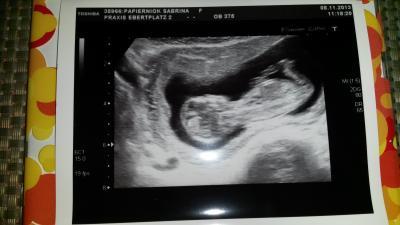

Hallo ihr Lieben. Danke fürs Daumen drücken ;) Es war heute super beim FA so toll alles gesehen. 2 verschiedene Ultraschall hat er gemacht. Vaginal u normal. Super sieht alles aus. :) ich habe mich die letzten 2 Tage ein wenig bekloppt gemacht aber natürlich für nichts :) habe auch meinen Mutterpass bekommen u bin für den 16.05.14 ausgerechnet u der Kümmel ist ~6cm groß. Ansonsten bin ich happy. Drücke allen anderen weiterhin die Daumen :) Schönes Weekend

Es freut mich, dass alles i.O. ist. Das Bild ist auch super geworden :)! Aber in der 13. SSW noch vag. US? Seltsam ... Schoenes Wochenende! Katja